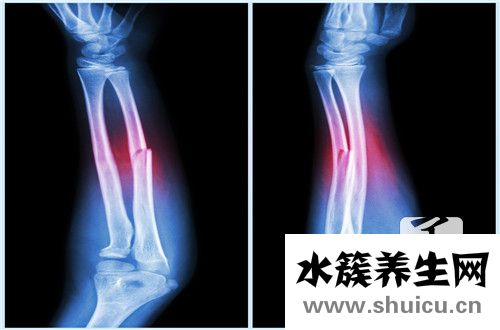

最先,肌肉有多種多樣,他們是由許多的體細胞產(chǎn)生的組織,每一個體細胞都就會有細胞質(zhì),因此,在肌肉切成片觀查時,我們難以見到體細胞的輪廊,見到數(shù)最多的便是細胞質(zhì)。

骨骼肌細胞中,每一個肌細胞挨近細胞質(zhì)上有很多細胞質(zhì),這是由于它是在發(fā)育階段中,由很多胚胎細胞經(jīng)細胞融合而成。

多核細胞帶有好幾個細胞質(zhì)。原生動物中大部分歸屬于等輻骨蟲的種群,及其一部分真菌類的菌根里,有當然產(chǎn)生的多核細胞。而人類肌肉中的肌細胞,也會在發(fā)育階段中產(chǎn)生多核細胞。這種細胞質(zhì)排序在在挨近體細胞邊沿的部位,造成較大 的體細胞內(nèi)室內(nèi)空間供肌原纖維根據(jù)。身體中有一些異常產(chǎn)生的多核細胞,比如當單核心球與巨噬細胞結合時,會造成超大多核細胞,有時候會隨著著炎癥反映,并與腫瘤的產(chǎn)生相關。